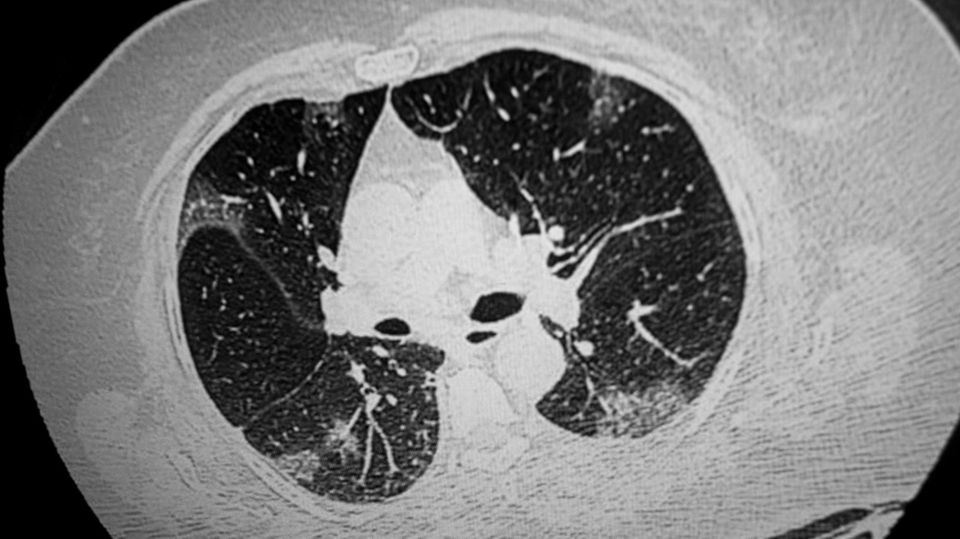

Schwere Verläufe zeigen unter anderem schon relativ früh Veränderungen in der Lunge, die sich mit einer Computertomographie feststellen lassen. Wir sagen dazu typische Milchglasinfiltrate, die aber nicht bei jedem Infizierten auftreten. Nur der Test auf Sars-CoV-2 erlaubt aber die eindeutige Diagnose.